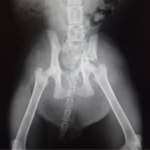

症例3:キルシュナーワイヤーのピンニングによる整復

ペルシャ猫 11ヶ月齢 雄

他院にて左大腿骨遠位の成長板骨折(salter-harrisⅠ型)が認められており、治療相談を目的として来院。当院にて、キルシュナーワイヤーを用いたピンニングにより骨折部位の整復を行いました。術後の経過は良好で、現在も経過観察中です。

術後レントゲン